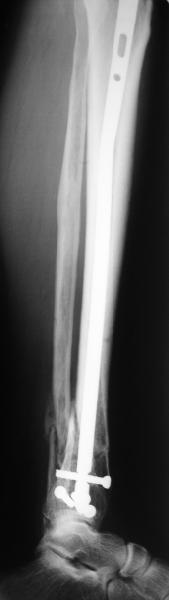

TDVC> Very interesting application, but is the final position in a

TDVC> little distal varus with some fibula distraction?

At least both the ankle mortise and tibial alignment look acceptable, don't they?

I am just trying to illustrate that prevention of 1)tibial valgus and 2)loss of reduction can be provided without fibular plating. Small changes of conventional nailing techniques allow to maintain reduction of the tibia reliably without adjunctive fibular stabilization.

In delayed cases acute length restoration performed only in the tibia may leave the fibula shortened thus change the mortise. So it is reasonable to restore length of both bones simultaneously by distractor and fix the fibula not with open reduction and plating but just by a single perQ screw. Example attached.